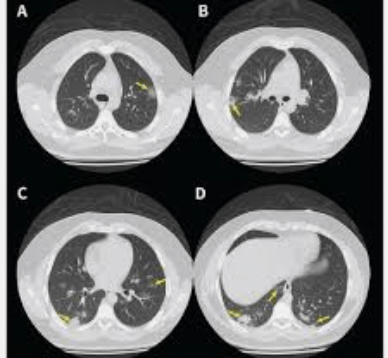

The results from the chest CT scan came back. When the ER physician was reading the report they noted that the images shown were in this plane since they divided the body into top and bottom.

What is the transverse plane?